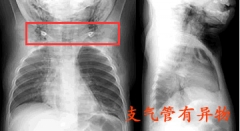

反复出现咳嗽咯痰 元凶是支气管有异物

反复咳嗽咳痰,大多数会想到是支气管炎、肺炎、肺结核等可能,在排除结核菌后,会持续性的消炎、止咳治疗,但是若消炎治疗持续不见好,那就需要警惕支气管有异物,有可能是...